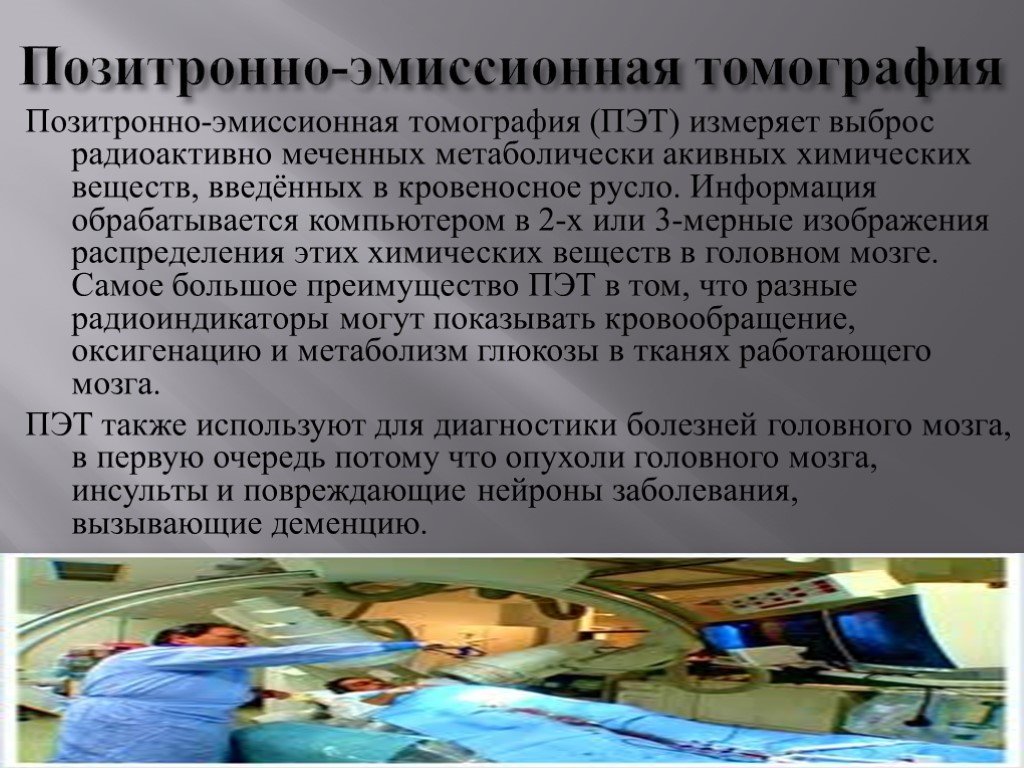

Компьютерная томография в неврологии презентация - 86 фото